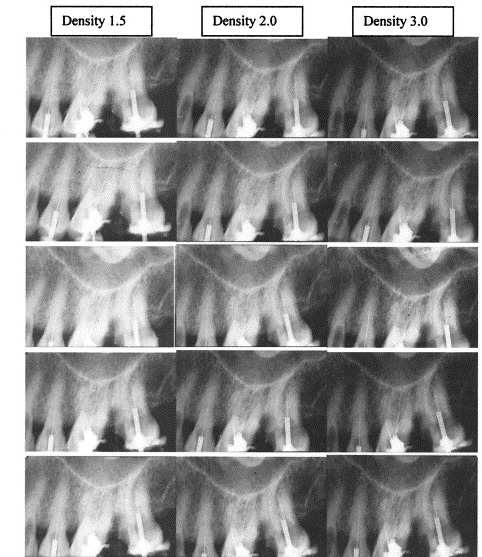

density

overall darkness of an image